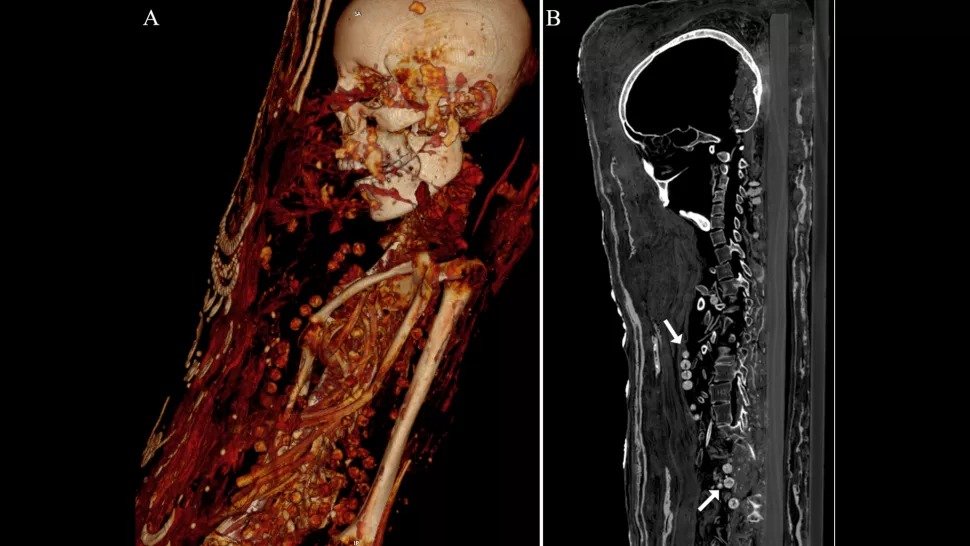

Preiskave CT (računalniška tomografija) kažejo, da je bila ena od treh ometanih mumij pokopana z organi (celo možgani), dve ženski pa s čudovitimi ogrlicami, so ugotovili raziskovalci.

CT skeniranje prikazuje kroglice ogrlice na vratu in telesu ženske. (Zesh et al., PLOS One, 2020).

CT je razkril tudi več zdravstvenih težav, vključno z ženskim artritisom.

Ženska, ki je umrla med 30. in 40. letom, je bila visoka približno 151 cm in je imela artritis v levem kolenu. Najstnik je po podatkih računalniške tomografije umrl med 17. in 19. letom in bil visok približno 156 cm.

V hrbtenici je imela benigni tumor, znan kot vertebralni hemangiom, ki je pogostejši pri ljudeh, starejših od 40 let, so povedali raziskovalci.

Obe ženski sta pokopani z veliko ogrlicami.